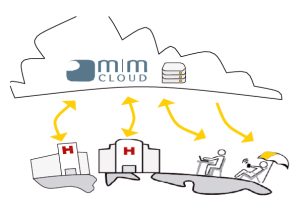

MIM Cloud ile Tüm Hasta Verilerini Tek Bir Yerde Saklayın!

MIMcloud – Güvenli Hasta Veri Depolama

MIMcloud, verilerinizi saklamak, paylaşmak ve incelemek için kolayca erişim sağlayan güvenli ve internet tabanlı bir tıbbi görüntü hizmetidir.

MIMcloud sayesinde:

- Tüm görüntülere ve verilere herhangi bir yerden uzaktan güvenli erişmek mümkündür.

- Tüm işler ve planlar, VPN gerekmeksizin bu buluta kaydedilebilir.

- Kullanıcılar, ofislerinde bulunan MIM araçlarının aynısını kullanarak planları uzaktan konturlayabilir ve inceleyebilir.

MIMcloud, görüntüleri ve RT verilerini başka kurumlarla ve ilgili doktorlarla kolayca paylaşma olanağı sunmaktadır.

Hastalar, sonuçlarına cep telefonlarıyla veya bilgisayarlarıyla erişebilir, acil durumlara karşı görüntüler ve plan verileri yedeklenebilir.

Felaket olasılığı dikkate alınarak, hastaların verilerinin uzakta yedeklenmesi mutlaka gereklidir.

Bu verileri korumanın en kolay yolu MIMcloud’dur.

MIMcloud Mirroring

Hasta listelerinizi MIMcloud™ hesabınıza otomatik olarak aktarabilirsiniz.

MIMcloud Mirroring aracı, yerel MIM veri tabanını MIMcloud’a otomatik aktarma olanağı sunmaktadır.

Bu otomatik özellik, kullanıcılara veriler nerede bulunursa bulunsun istedikleri yerden çalışma olanağı sunmaktadır.

- Bir doktor ofisinde çalışabilir, yaptığı işleri kaydedebilir, sonra evine gidebilir ve bıraktığı yerden çalışmaya devam edebilir.

- Verileri elle aktarması gerekmez.

MIM’i nerede kullanırsanız kullanın, aynı verilere erişebilirsiniz.